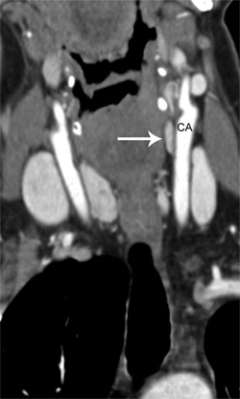

Figure 1a. Parathyroid 4D-CT showing a parathyroid adenoma in an abnormal position within the carotid sheath, missed during a prior surgery. CA= Carotid artery.